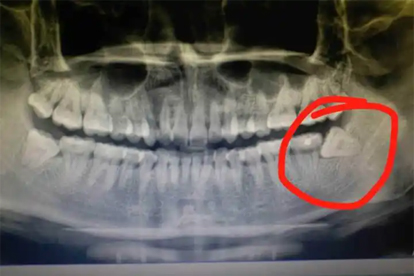

拔掉智齒后注意事項

拔掉智齒后需注意傷口護(hù)理、飲食調(diào)整、疼痛管理、出血控制和預(yù)防感染。拔牙后24小時內(nèi)避免漱口和劇烈運(yùn)動,選擇軟質(zhì)食物,按醫(yī)囑使用藥物,并觀察異常癥狀及時就醫(yī)。